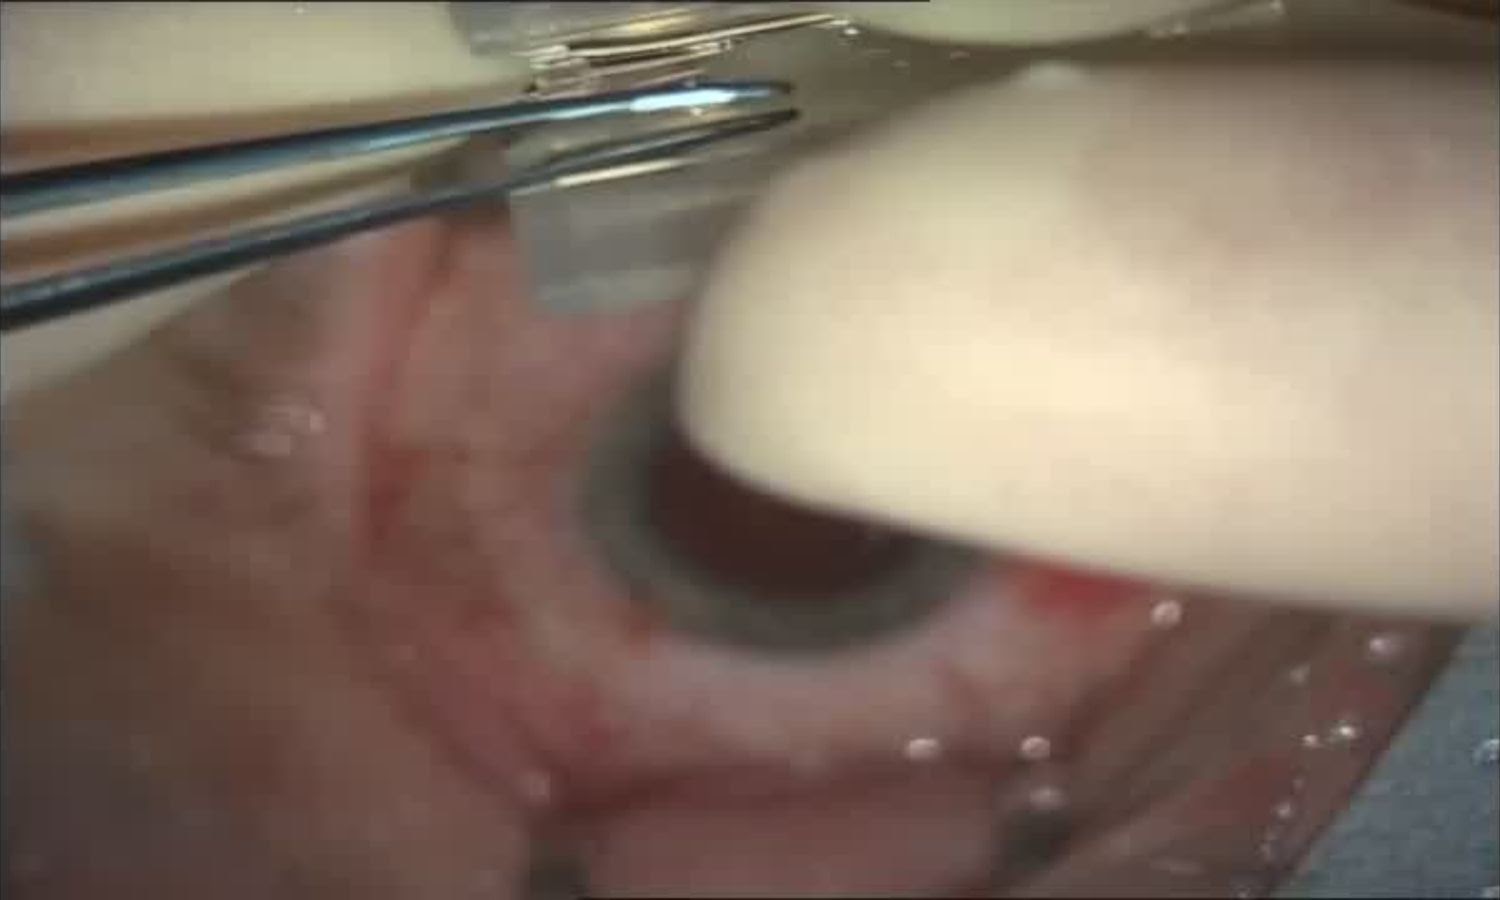

В пинцете — первая линза, которую сворачивают в трубочку и помещают в одноразовый инжектор:

Далее в сделанный ранее основной прокол вставляется инжектор, который вводит линзу в освободившееся пространство. Под силами собственной упругости (и обладая памятью формы) линза разворачивается, а её «лапки» упираются в края капсулы хрусталика. Чем лапок больше, тем лучше. Чем меньше свободного пространства остаётся в мешке — тем тоже лучше.

Дальше задача хирурга — правильно сориентировать линзу по оси вращения. Спустя какое-то время линза окончательно «сядет», а форма капсулы хрусталика надёжно «обнимет» её. Затем вымывается вископротектор из-под линзы (и над ней) иии готово.